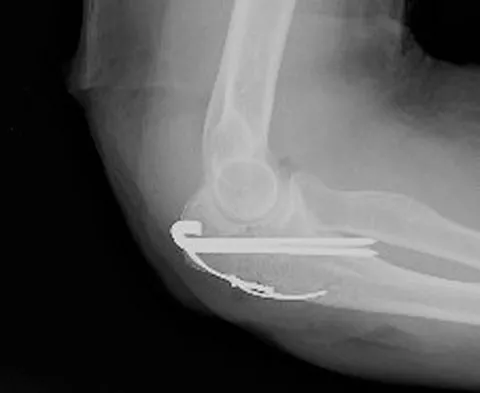

A 78-year-old woman falls onto her nondominant left elbow and sustains the injury shown in Figure 5. What treatment option allows her the shortest recovery time and highest likelihood of good function and range of motion?

Explanation

Total elbow arthroplasty has become the treatment of choice for complex, comminuted distal humeral fractures in patients older than age 70 years. It yields a faster recovery with more predictable functional outcomes, although limitations of lifting weight of more than 5 pounds must be followed to avoid loosening. Kamineni S, Morrey BF: Distal humeral fractures treated with noncustom total elbow replacement. J Bone Joint Surg Am 2004;86:940-947.